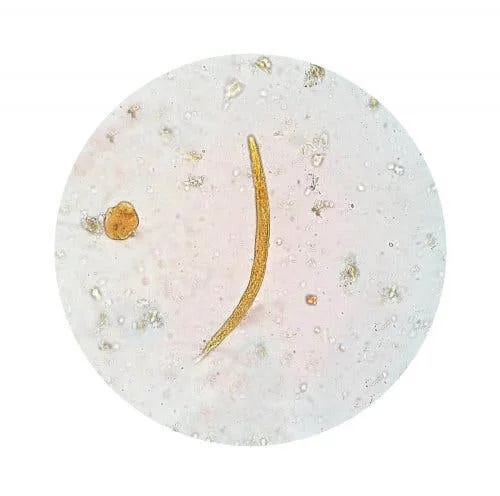

Cea mai indicată tehnică de diagnostic este examinarea microscopică a scaunelor. Aceasta include microscopie cu contrast de fază sau cu colorare, folosindu-se tehnici precum Ziehl-Neelsen sau Kinyoun. De asemenea, profesioniștii din domeniul medical apelează și la microscopia cu imunofluorescență.